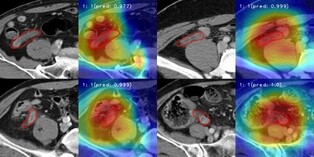

CT영상으로 충수염 자동 판독하는 AI 모델 개발…‘진단 정확도 89.4%’

이한희 /

2022.11.23